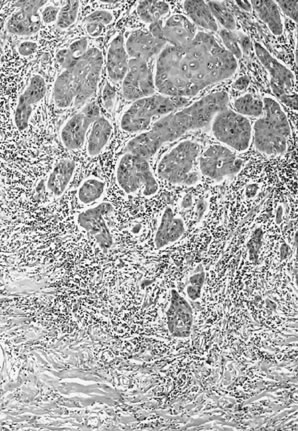

In normal squamous epithelium, the basal cells divide and thereafter differentiate in a fixed postmitotic fashion. As maturation occurs, cytoplasm is acquired, granules of prekeratin are formed, and the cellular outline and nucleus eventually are lost in the superficial keratin layer. In VIN lesions, the epithelial cells continue to exhibit large nuclei with nuclear hyperchromasia as they progress upward. These cells are atypical. Mitotic figures are found elsewhere than in the basal layer and are often atypical in appearance. Multinucleation implies impairment of the cell division mechanism. Nuclear pleomorphism, hyperchromasia, and loss of maturation are evidence of abnormal development (Figs. 3 and 4). Finally, the rate of epithelial cell division and the number of cells undergoing cell division may be increased, resulting in an increased density of the cell population.

Fig. 3. Vulvar intraepithelial neoplasia (VIN) 3 (severe dysplasia), basaloid type. This intraepithelial lesion is composed of relatively uniform epithelial cells with little maturation and nuclear hyperchromasia.

Basaloid type: These are characterized by relatively uniform cells without significant maturation from the basal-parabasal cells (Fig. 3)